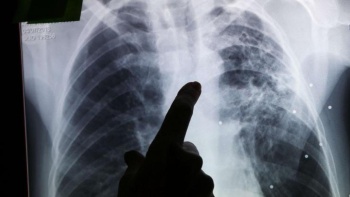

В Крыму растет заболеваемость детей туберкулезом

Рост показателей заболеваемости туберкулезом у детей, прежде всего подростков, в Крыму обусловлен потоком в республику беженцев из новых регионов РФ с соответствующим диагнозом, которые не делали прививки и не имели возможности проходить регулярные профосмотры. Об этом в эфире радио "Спутник в Крыму" сообщила главный внештатный детский специалист фтизиатр Минздрава Крыма Нина Яворская, - передает Керчь.ФМ.

По данным Роспотребнадзора, в России заболеваемость туберкулезом среди детей до 14 лет за последние полгода выросла на 17% по сравнению с прошлым годом.

По словам Яворской, в Крыму рост показателей заболеваемости подростков отмечается очень значительный - на 52%. Фиксируется увеличение числа заболевших и среди детей более младшего возраста - на 1, 4% по сравнению с прошлым годом.

Основная причина, по словам эксперта, связана с особенностями выявления таких больных: по месту их пребывания, а не регистрации. В результате на статистике отражается ситуация, характерная для жителей новых регионов России, которые сейчас проживают в Крыму.

"Среди детей до 14 лет 25% - это жители Херсонской и Запорожской областей. Среди подростков такой показатель еще выше - 37%". Поскольку диагноз выставлялся в Крымском республиканском клиническом центре фтизиатрии и пульмонологии и в дальнейшем дети получают лечение у нас в центре, эти случаи заболеваемости регистрируются за республикой Крым", - пояснила Яворская.

Врач подчеркнула, что чаще всего болеют самые маленькие дети - до 3 лет, и подростки 12 - 17 лет.

В отношении постоянного населения Крыма рост заболевания туберкулезом сегодня не наблюдается, но "расслабляться не нужно", предупредила эксперт.

"Потому что туберкулез - это инфекционное заболевание, которое передается воздушно-капельным путем, и ввиду того, что были сложности с профилактическим осмотром в соседних наших новых регионах, есть высокий риск инфицирования и у нас, в Республике Крым. И этот риск растет. Поэтому нужно не забывать о профилактических мероприятиях: своевременно обследовать своих детей и следить за своим здоровьем", - сказала врач.

Как правило, речь идет о невакцинированных пациентах, среди новорожденных детей-крымчан это порядка 5%, отметила Яворская. В зоне особого риска также дети, имеющие сопутствующие хронические заболевания, добавила она.

По словам Яворской, туберкулез может маскироваться под разные заболевания. Среди главных симптомов, позволяющих его заподозрить: постоянная немотивированная слабость и утомляемость, ухудшение и отсутствие аппетита, потеря массы тела, а для малышей - отсутствие прибавки, незначительное, но длительное повышение температуры, продолжительный кашель.

"Если такие симптомы есть, надо незамедлительно обратиться к врачу. Но, к сожалению, более чем в 50% случаев туберкулез у детей протекает бессимптомно. Для этого и существуют внутрикожные диагностические пробы, чтобы выявить даже не само заболевание, а риск развития заболевания. То есть начало латентной туберкулезной инфекции, так называемого фактора инфицирования. И затем детские специалисты назначают профилактические лечение противотуберкулезными препаратами. Вот это очень важно", - заключила эксперт.